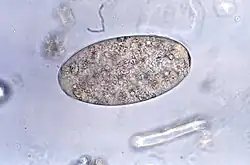

Huevo de Fasciolopsis buski

Los adultos producen más de 25.000 huevos al día, que tardan hasta siete semanas en madurar y eclosionar a 27-32 °C. Los huevos no embrionados, inmaduros, se descargan en el intestino y las heces. En dos semanas, los huevos se embrionan en agua, y después de aproximadamente siete semanas, los huevos liberan pequeños organismos parásitos llamados miracidios, que invaden un caracol, el huésped intermediario adecuado. Varias especies de los géneros Segmentina y Hippeutis sirven como huéspedes intermediarios. En el caracol, el parásito sufre varias etapas de desarrollo (esporoquistes, rediae y cercarias). Las cercarias se liberan del caracol y se enquistan como metacercarias en plantas acuáticas tales como castaño de agua, callo de agua, loto, bambú y otras plantas comestibles. El huésped final de los mamíferos se infecta al ingerir metacercarias en las plantas acuáticas. Después de la ingestión, las metacercarias excretan en el duodeno en aproximadamente tres meses y se unen a la pared intestinal. Allí se desarrollan en trematodos adultos (20 a 75 mm por 8 a 20 mm) en aproximadamente 3 meses, unidos a la pared intestinal de los huéspedes mamíferos (humanos y cerdos). Los adultos tienen una vida de aproximadamente un año.